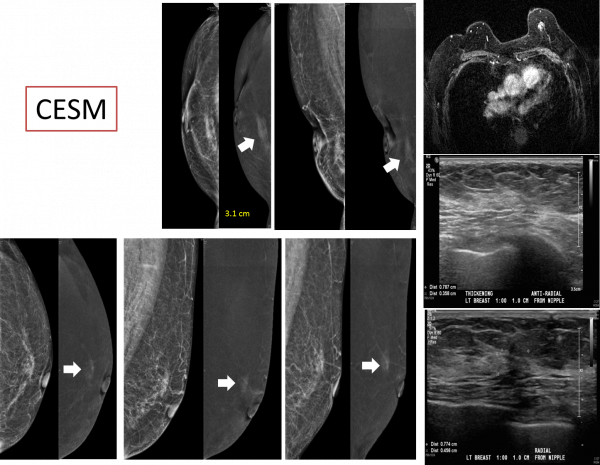

Contrast-enhanced Spectral Mammogram (CESM)

對比增強能譜乳房攝影

若乳癌與乳腺間的對比不夠,乳癌會無法在數位乳房攝影(2D)被偵測出來。腫瘤若有不正常血管,透過施打對比劑(或叫顯影劑)後(與電腦斷層顯影劑同),腫瘤會被顯影出來,增加腫瘤被偵測出來的機會(增加對比)。正常組織與病灶顯影程度不同,經過高、低能量X光的照射與相減,即可將有不正常血管的腫瘤或癌症顯現出來。對比增強能譜乳房攝影有助於腫瘤或乳癌的診斷,對超音波、乳房攝影影像中發現的不確定病灶,鈣化、不對稱、結構扭曲亦可解決其問題,確立診斷。